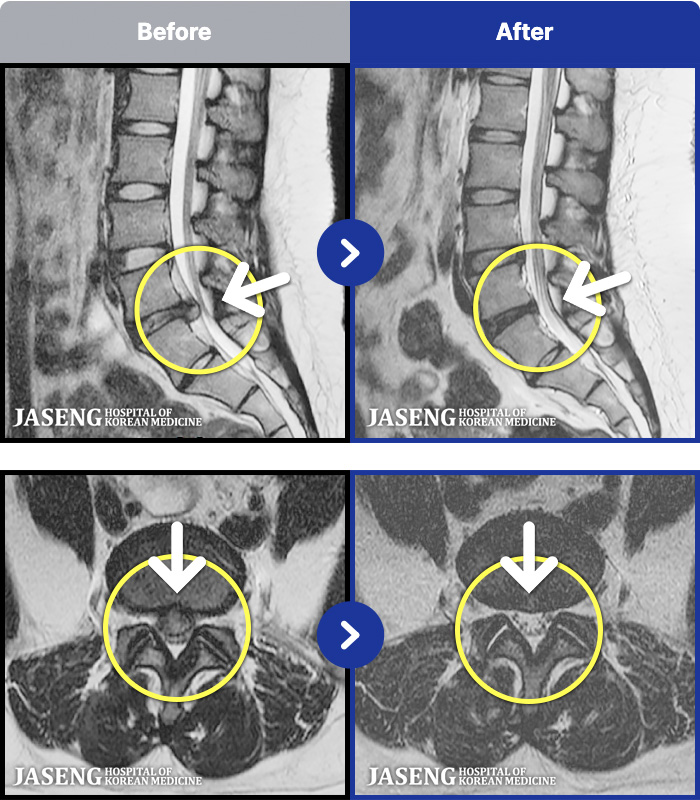

MRI ġ

MRI ũ ʸ Ȯϼ.